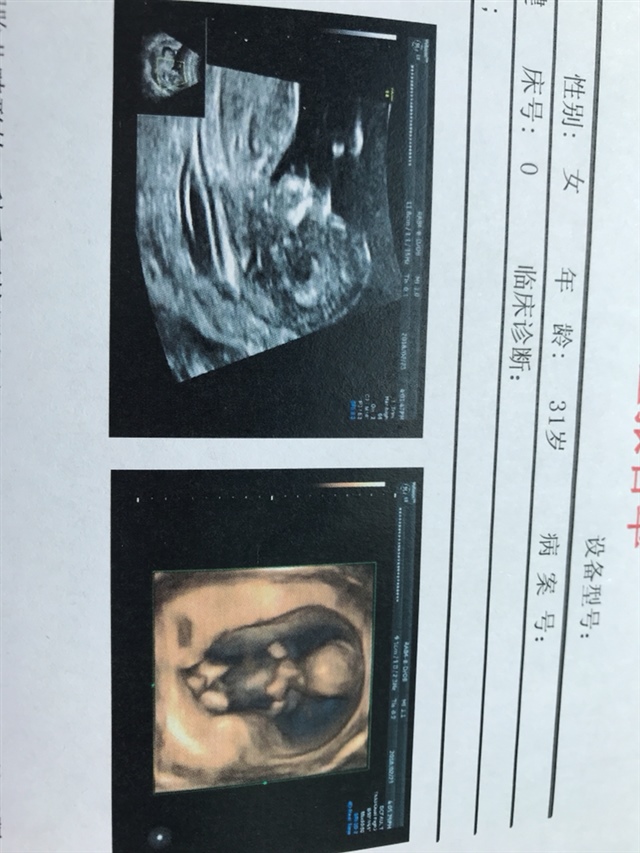

孕7周+3天

孕25周+1天